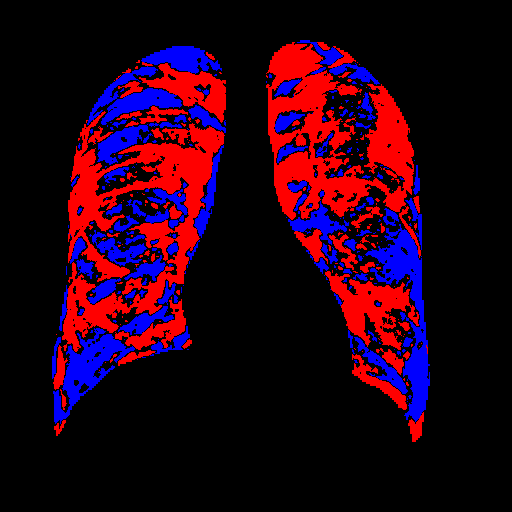

4.1 Qualitative Evaluation of Healthy Counterpart Generation

Example images from the disease COVID-19 Radiography Database and their generative healthy counterparts are given in figure 2. The images on the far left are instances of the lung opacity class from the real images in the dataset. The images in the middle column are examples of the generated healthy counterfactuals obtained via latent space diffusion, with RadBERT-guided textual-conditioning via a conditional prompt “normal chest x-ray”. A total of 75 diffusion inference steps are used with image conditioning strength=0.85 and guidance scale=7.5. (The former indicates the level of constraint on changes to the original input image and the latter is the weight given to the textual encoder conditioning in the generation of the image, ranging over [0,1] and [0,9], respectively).

Side-by-side inspection of the generated healthy counterfactuals (as per fig. 2) suggests that, as required, only minimal perturbation is made to the original image with respect to healthy pixels -i.e. localized image sites without structural medical defects. (In the top row, the medical structural defect in the original image is due to a lung opacity, and characterized via a relatively complex interaction between the imaging modality and subject manifesting as ‘gaps’ in the corresponding portions of the lung scan). The healthy/non-healthy discrepancy maps in all of these cases are obtained via masked subtraction of the original image from the generated image (the ground truth segmentation masks correspond to the broad area of interest –i.e. the complete lung). The generated healthy tissue is thus a subset of the mask and is shown in the final column of fig. 2 for the respective cases.

In the context of a VANT-GAN[20]-based approach, this highlighted material constitutes the diagnostic counterfactual visual attribution, i.e. the selection of material relevant to the diagnosis of the unhealthy condition. Healthy counterfactual generation was performed for the complete datasets in the three unhealthy classes, i.e Lung opacity, Viral Pneumonia and COVID, examples of which are given in fig. 3 for the three classes (all of the generated healthy counterfactuals from this experiment can be found on https://huggingface.co/ammaradeel/diffusionVA). Visual inspection indicates that the generated counterfactuals are, in general, visually plausible with minimal perturbation made to the unhealthy image overall. Moreover, the healthy counterpart generation does not appear to unnecessarily affect aspects of the images unrelated to the medical condition, the model selectively making changes to the unhealthy regions in a structurally plausible manner, e.g. generating missing portions of the lung without generating extraneous lung material where it would be expected to normally exist (e.g. in the abdominal cavity).